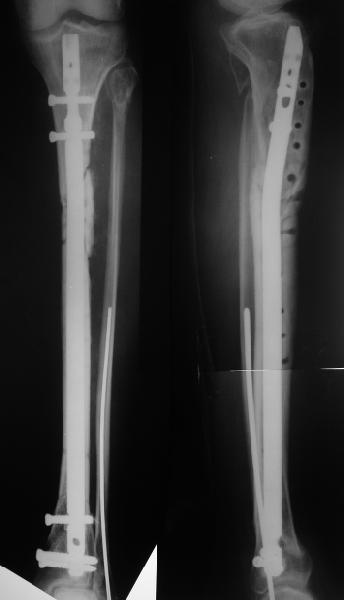

Декабрь 200322 июня 2004

В декабре прошлого года обсуждался случай бамперного перелома голени, когда молодой женщине в одной из больниц Москвы неудачно был выполнен остеосинтез гвоздем - это обсуждение можно просмотреть здесь, снимок тогдашний прилагаю.

Вчера поступила к нам в отделение. Клинически определяется приличная подвижность, градусов 35 в переднезаднем направлении. На снимках еще видны фиксированная тоникм стержнем уже сросшаяся малоберцовая кость, и тоже сросшийя перелом дистального метадиафиза большеберцовой костибез признаков хирургической фиксации (?). Сегодняшний снимок также в приложении.